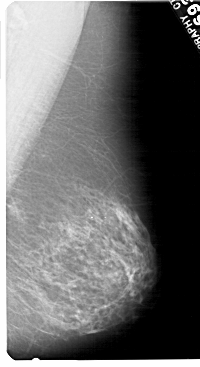

A_1480_1.RIGHT_CC

RIGHT_CC LINES 5491 PIXELS_PER_LINE 3196 BITS_PER_PIXEL 12 RESOLUTION 43.5 NON_OVERLAY

RIGHT_MLO LINES 5491 PIXELS_PER_LINE 2986 BITS_PER_PIXEL 12 RESOLUTION 43.5 NON_OVERLAY